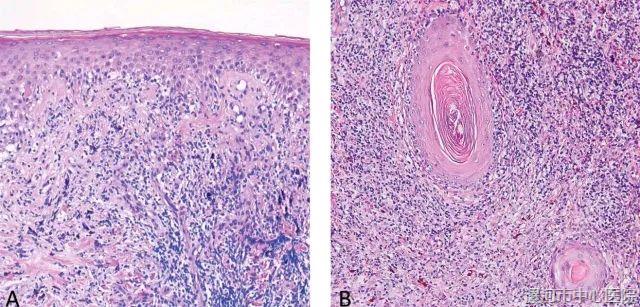

图3. (左)真皮表皮交界处皮炎,且真皮内有以组织细胞为主的炎症细胞浸润,似有模糊肉芽肿表现。(右)毛囊周边的炎症及弥漫性淋巴细胞、组织细胞浸润。